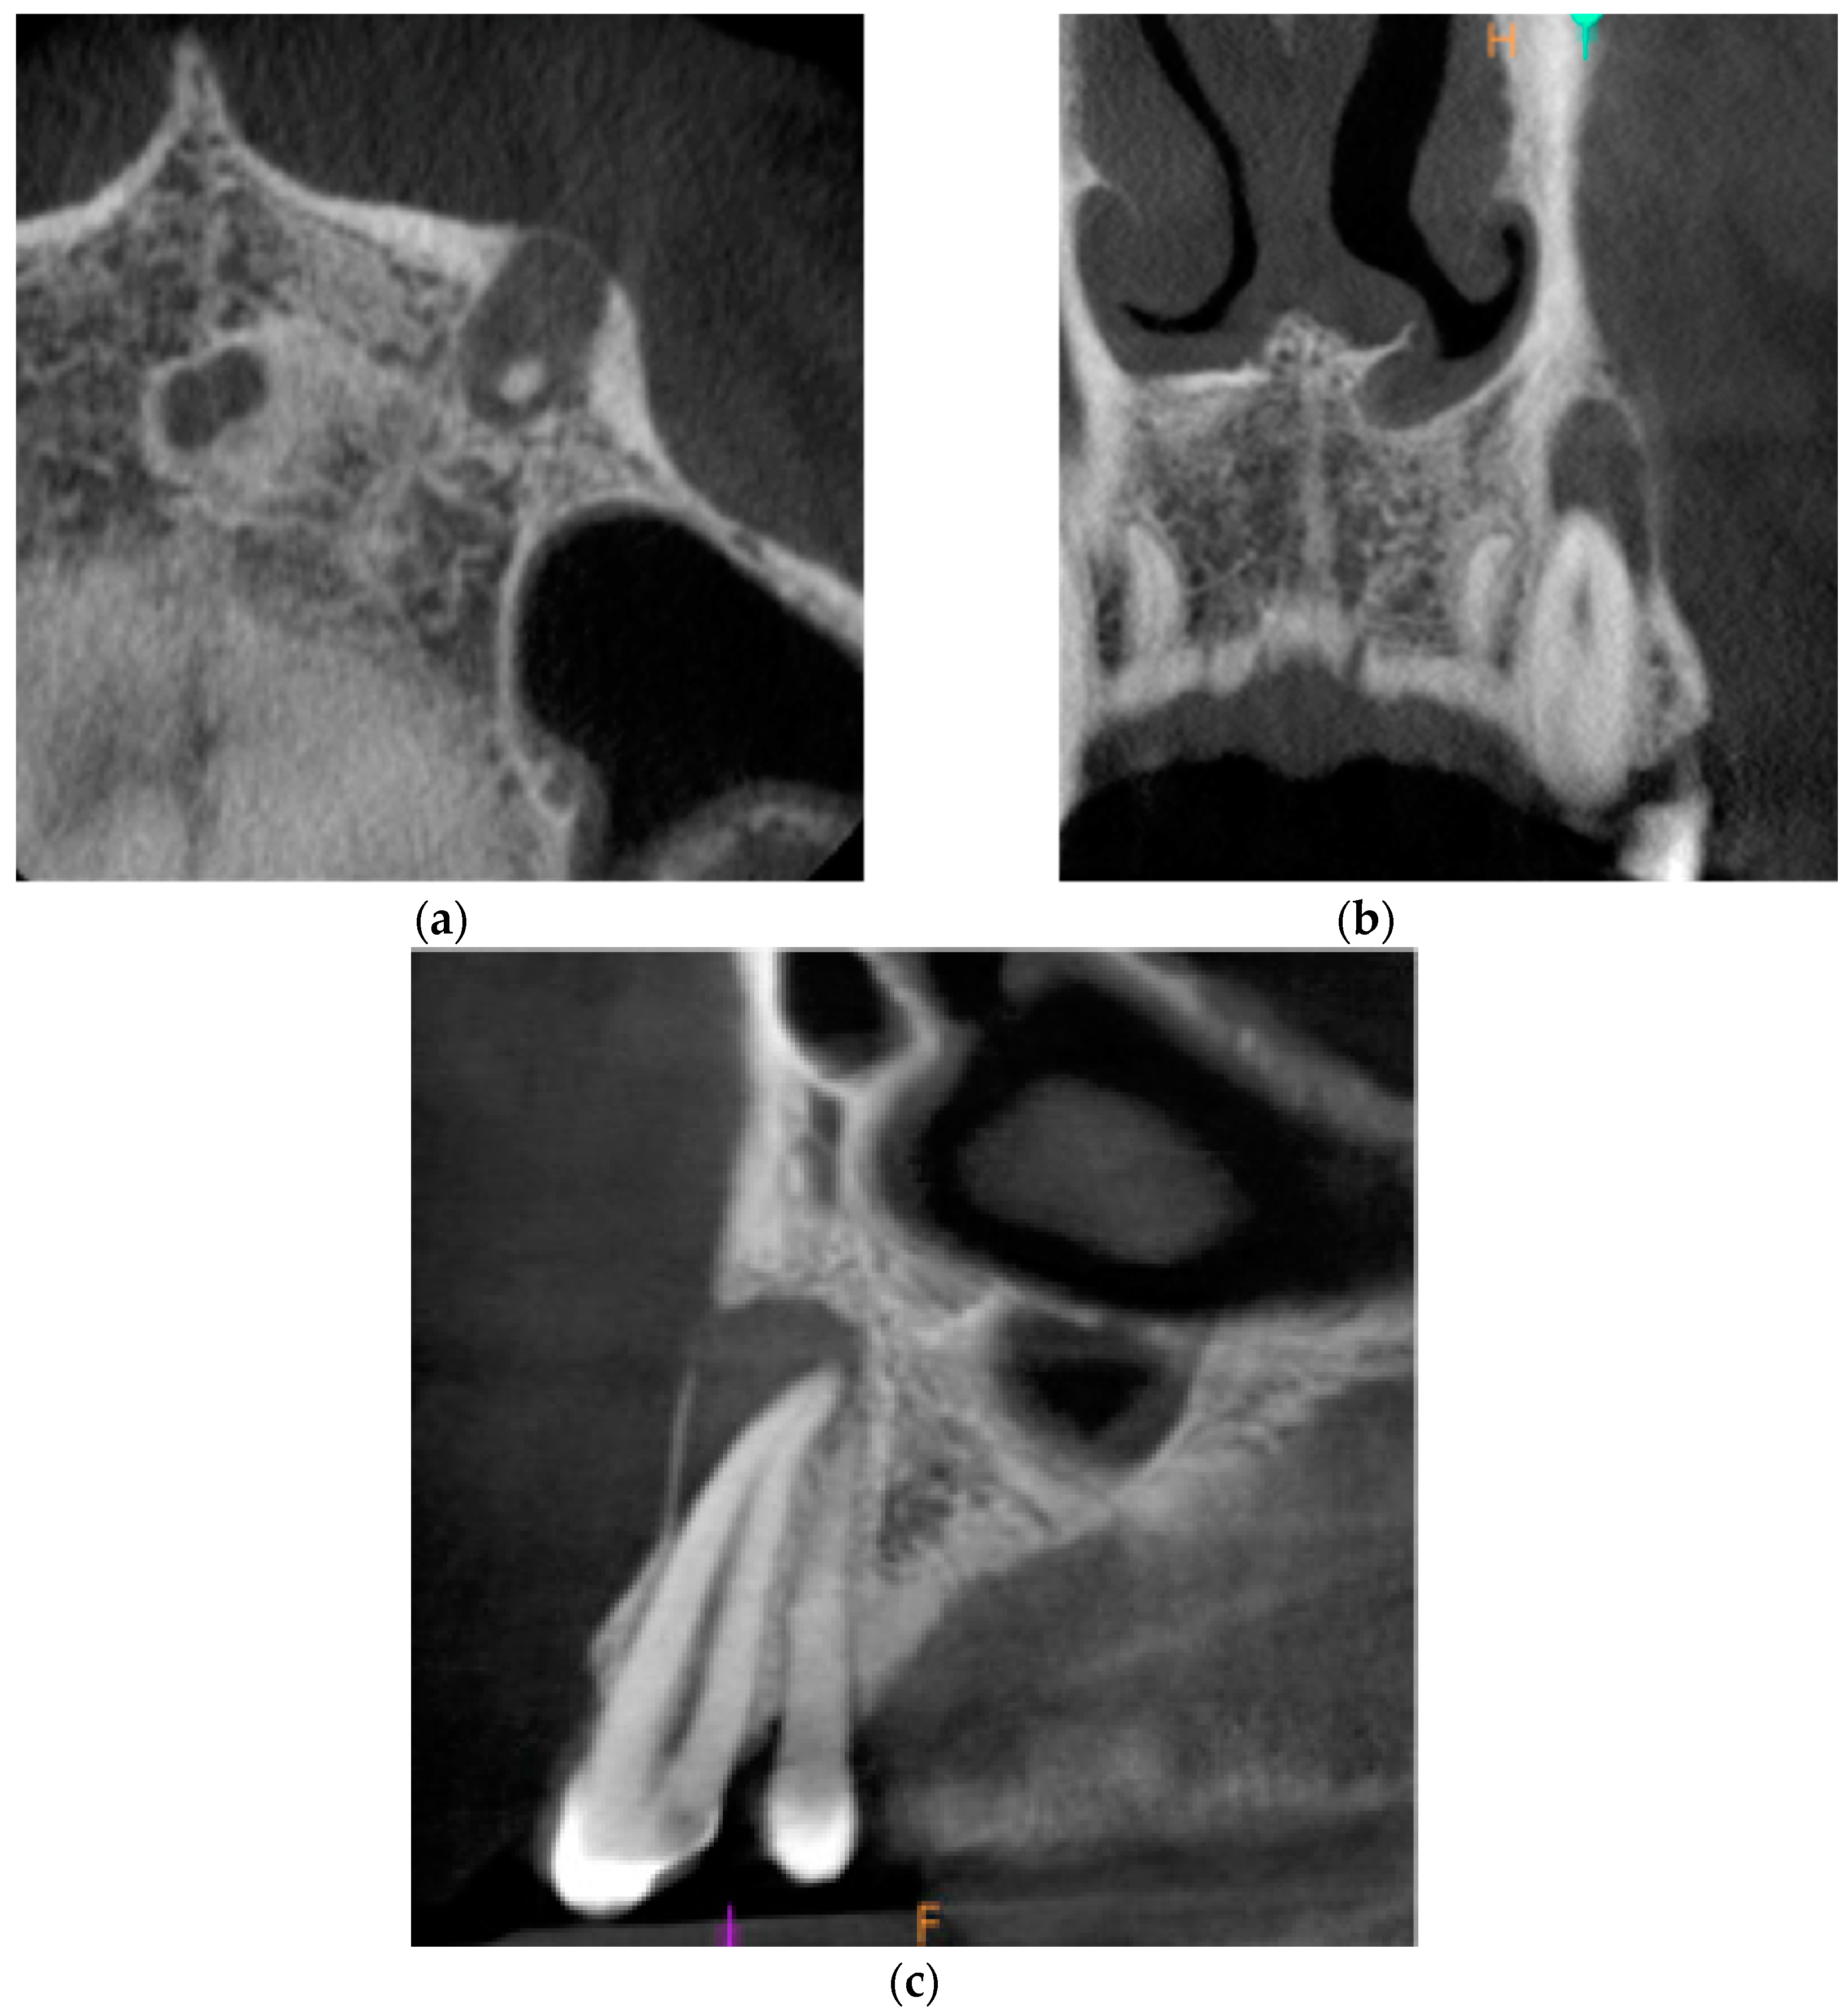

Cone-beam computed tomography (CBCT) was performed. The periapical lesion was measured with the use of CS 3D Imaging v3.5.18 Software (Carestream Health Inc., Trophy, Croissy-Beaubourg, France). The measured dimensions of the lesion were 9.0 × 7.2 × 9.9 mm. The CBCT images of the periapical lesion are presented in Figure 1.

Figure 1. Preoperative cone beam computerized tomography (CBCT) images presenting the periapical lesion around the root of tooth no. 23 (date of CBCT examination: 22 May 2020): (a) axial view; (b) coronal view; and (c) sagittal view.